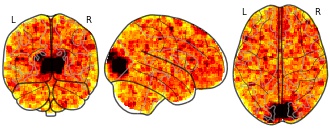

EmailClick to copy linkLink copied Cite(2021). Medial frontal cortex activity predicts information sampling in economic choice: Macaque OFC template (RSA t-stats) [Dataset]. http://identifiers.org/neurovault.image:440415niftiAvailable download formatsUnique identifierhttps://identifiers.org/neurovault.image:440415Dataset updatedJun 10, 2021License

Cite(2021). Medial frontal cortex activity predicts information sampling in economic choice: Macaque OFC template (RSA t-stats) [Dataset]. http://identifiers.org/neurovault.image:440415niftiAvailable download formatsUnique identifierhttps://identifiers.org/neurovault.image:440415Dataset updatedJun 10, 2021LicenseCC0 1.0 Universal Public Domain Dedicationhttps://creativecommons.org/publicdomain/zero/1.0/

License information was derived automaticallyDescriptionFSL3.3

Collection description

Unthresholded Z-statistic maps for all analyses in Kaanders et al. (2020).

Subject species

homo sapiens

Modality

fMRI-BOLD

Analysis level

group

Cognitive paradigm (task)

multi-attribute decision making task

Map type

Other